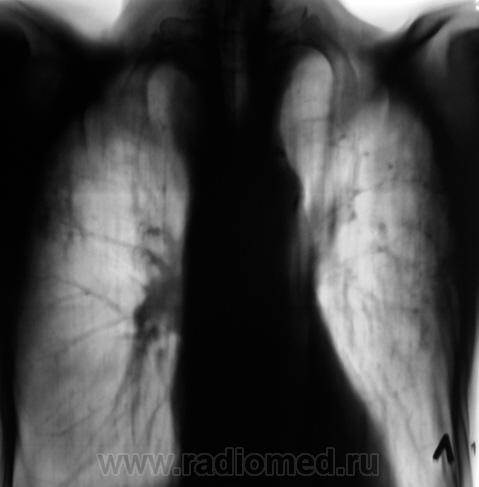

Хотелось-бы акцентировать внимание на срезе 7 см. Как на Ваш взляд, помеченное желтыми стрелками?

Фокусная тень в каверне с дорожкой к корню. Оригинально-с, сказал бы поручик Ржевский.

Сомнения вызвала тень, помеченная желтой стрелкой. На наш взгляд, это был растущий гриб. Однако возобладало мнение, что "это" участок некроза, так как не было "симптома погремушки"

Однако, в последующем, лабораторно наличие "гриба" было доказано.

И, уже через год, при плановом обследовании данного пациента, мы "поимели" такие картинки.